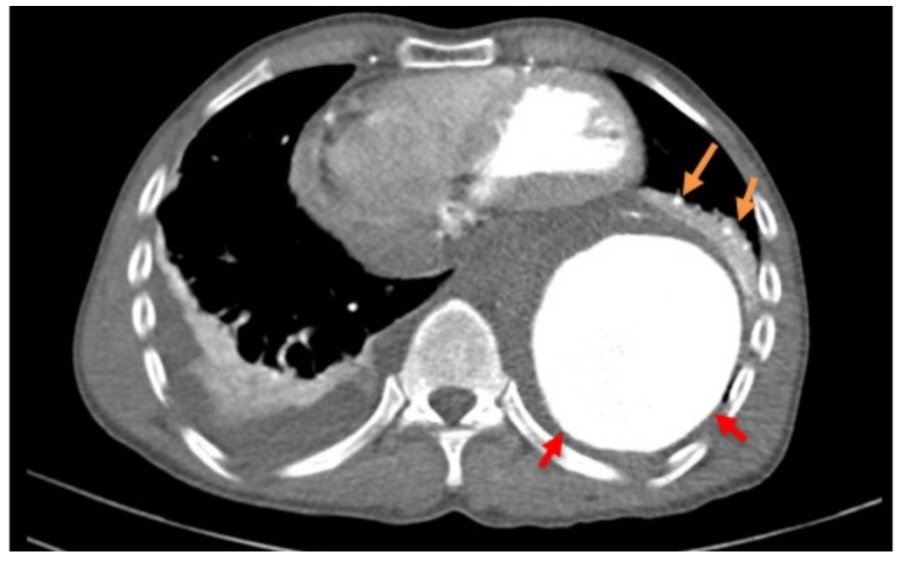

Tại khoa cấp cứu Bệnh viện S.I.S, kết quả chụp CTA cho thấy, ông T. bị Phình động mạch chủ ngực đã vỡ gây tràn máu ra ngoài thành mạch xung quanh động mạch chủ ngực đoạn xuống và màng phổi hai bên, nguy cơ tử vong cao. Sau hội chẩn, các bác sĩ đã tiến hành can thiệp nội mạch cấp cứu đặt stent graft nhằm ngăn chặn máu chảy ào ạt từ túi phình ra ngoài ổ bụng gây tử vong. Sau 30 phút, ca can thiệp thành công. Hiện ông T. đã giảm đau ngực, đang được tiếp tục theo dõi.

CT lồng ngực có tiêm thuốc cản quang: máu tụ quanh phình động mạch chú (mũi tên cam); phình động mạch chủ ngực đoạn xuống (mũi tên đỏ)

CT lồng ngực có tiêm thuốc cản quang: máu tụ quanh phình động mạch chú (mũi tên cam); phình động mạch chủ ngực đoạn xuống (mũi tên đỏ)